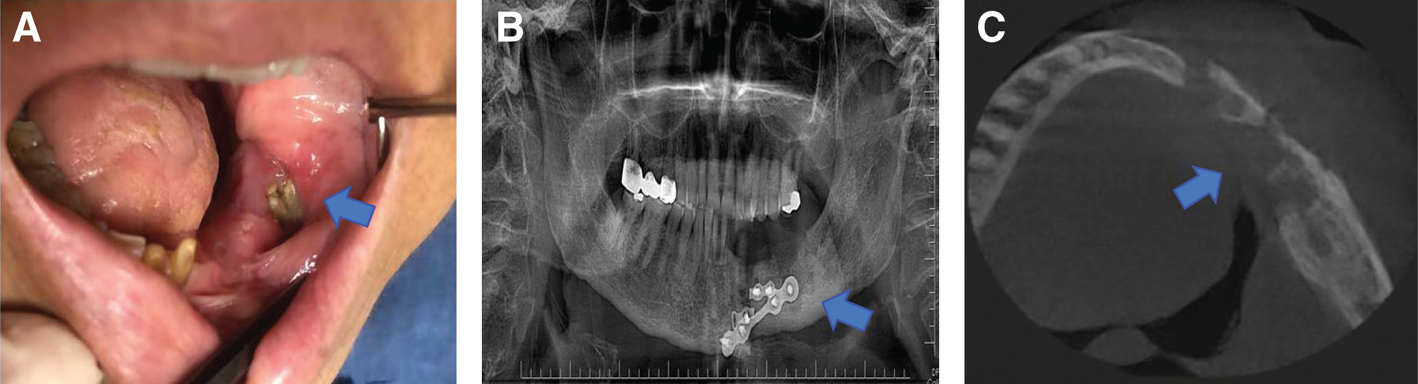

The ORNJ may manifest with a variety of signs and symptoms after RT or CCRT. Common ORNJ symptoms include facial deformity, discomfort, foul breath (halitosis), dysgeusia, dysesthesia or anesthesia, trismus, difficulties with mastication, deglutition, difficulty eating and speaking, intraoral or orocutaneous fistula formation, pathologic fracture, and localized or systemic infections (18) (Figure 1A-C). ORNJ severely worsens patients’ quality of life (QoL) after the oncologic therapy as a result of these serious symptoms and/or their consequences (19). Research on this topic is limited despite the fact that practically all studies demonstrate that ORNJ negatively affects health-related QoL (HRQoL) measurements (2023). The HRQoL assessment gathers data on the psychosocial health of patients as well as the relevance of the specific disease state and its treatment. In light of this, HRQoL-based studies are growing in popularity as useful methods for evaluating functional and psychosocial outcomes in conjunction with relapse and survival rates in a variety of disorders (24).

Figure 1. Osteoradionecrosis of the lower jaw in the left retromolar region (blue arrow). A: clinical intra-oral view. B: panoramic radiograph image. C: axial cone-beam computed tomography image.